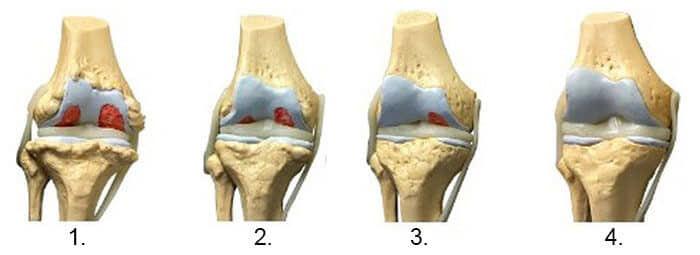

1. Lipsa alimentației articulației. Țesutul cartilaginos se distruge.

2. Regenerarea țesutului cartilaginos al articulației după 2 săptămâni de

utilizare a „Steplex”.

3. Regenerarea țesutului cartilaginos al articulației după 3 săptămâni de

4. Articulație sănătoasă după terminarea cursului cu „Steplex”.